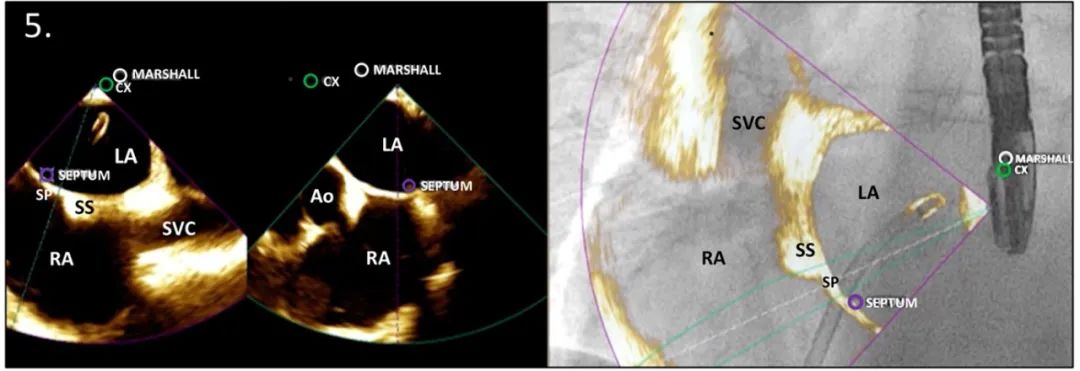

标记TSP的位置

一旦穿过卵圆窝,释放了房间隔的张力,可以交替TEE的双腔和短轴切面,用第三个标记物确定TSP的位点,以减少因硬件向后移动时,定位丢失的风险。

缩写注释:Ao: 主动脉;CX,左回旋动脉;LA: 左心房;LAA: 左心耳;RA: 右心房;SP: 原发隔;SS: 继发隔;SVC: 上腔静脉;TEE: 经食管超声心动图;TSP: 经房间隔穿刺;白或黑色箭头,卵圆窝处的房间隔。